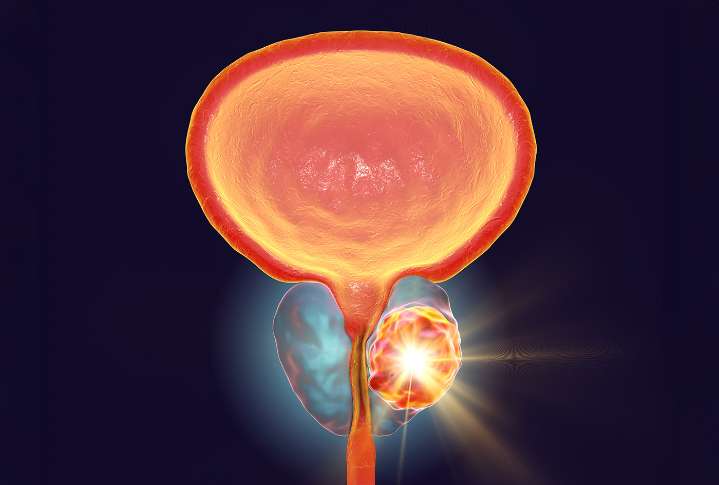

A hormone produced by the thyroid gland may drive the growth of prostate cancer , and blocking its receptor could form the basis of a new treatment strategy, according to an international research team from Umeå University, Sweden, and the Medical University of Vienna, Austria. The research, published in Molecular Cancer , showed that prostate cancer cells multiple rapidly when the thyroid hormone triiodothyronine (T3) activates its receptor thyroid hormone receptor beta (TRβ).

“The results indicate that the receptor in question is a driving force in the growth of cancer. Substances that block it could thus be a target for future drugs against prostate cancer,” said study leader Lukas Kenner, MD, visiting professor at Umeå University.

In contrast, blocking TRβ with a selective anta